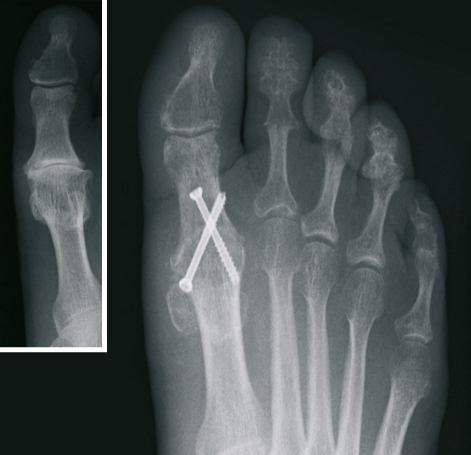

Der Hallux valgus (Ballenzehe)

Beim Hallux valgus - im Sprachgebrauch häufig Ballenzehe genannt - handelt es sich um eine Abweichung der Großzehe nach außen, kleinzehenwärts. Diese Fehlstellung tritt häufiger bei Frauen auf. Die genaue Ursache ist nicht geklärt, sicherlich spielen falsches Schuhwerk und Erbanlagen eine große Rolle. Die unterschiedlichen Ausprägungen sind durch eine zunehmende Fehlstellung, verbunden mit Schmerzen, gekennzeichnet.

Von einer operativen Korrektur ohne Vorhandensein von Schmerzen, d. h. aus rein kosmetischer Sicht, ist abzuraten. Bei Auftreten von Schmerzen im Bereich der Großzehe ist die operative Vorgehensweise jedoch die einzig dauerhafte therapeutische Möglichkeit.

Nach ausführlicher Untersuchung, Betrachtung der individuellen Erfordernisse, sowie Analyse der Röntgenbilder wird die Behandlung festgelegt. Hierbei kommen verschiedene international anerkannte Operationsverfahren zur Anwendung. Wir verwenden dabei modernste Platten und Schrauben aus Titan.

In Abhängigkeit vom Ausmaß der Operation bzw. dem zur Anwendung kommenden Verfahren, haben wir die Möglichkeit sowohl eine ambulante, als auch eine stationäre Behandlung durchzuführen.